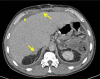

Systemic sarcoidosis is a disease of unknown etiology, with the liver being the third most commonly affected organ. Most cases of hepatic sarcoidosis are not clinically apparent, but a few can progress to liver cirrhosis, portal hypertension and ultimately liver failure. The diagnosis of hepatic sarcoidosis is difficult, considering that no single laboratory test or radiographic finding can definitively diagnose this systemic disease. Diagnosis of hepatic sarcoidosis relies heavily on histopathologic evaluation of two or more organs, a diagnostic modality that is invasive and may not be applicable to all patients. The treatment of hepatic sarcoidosis is challenging, with no large randomized controlled trials done to date. Physicians must be aware of the complications of hepatic sarcoidosis, and must include the same in the differential diagnosis of liver cirrhosis. We present a case of hepatic sarcoidosis complicated by portal hypertension and liver cirrhosis.